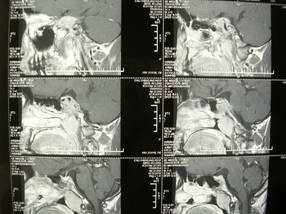

男、30、发现鼻咽部肿瘤侵犯海绵窦,未发现明显淋巴肿。请问国内那家医院治疗鼻咽部肿瘤最好?手术以何种方式为主?病灶可否全部切除?急切期待的大家的帮助。

扫描示鼻咽腔不对称,中度狭窄,右侧咽隐窝消失,局部软组织肿块,鼻咽右侧壁增厚形成肿块,突入鼻咽腔,肿块平扫呈等密度,肿块向深部侵润,右侧翼内外肌受侵,右侧咽旁间隙变窄;向后生长,头长肌界线欠清,向后上生长侵犯同侧颈动脉鞘区。双侧海绵窦增宽,内见软组织影与鼻咽部肿块相连。考虑鼻咽癌。鼻咽癌主要是放射治疗,且效果较好;到当地有治疗设备较大医院治疗即可。

鼻咽部新生物(纤维血管瘤?鼻咽癌?)侵犯右侧中颅窝底及右侧海绵窦;建议必要时活检定性。

典型鼻咽癌侵犯右侧海绵窦(对放疗敏感)